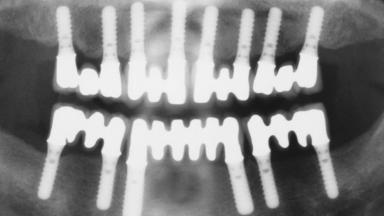

Immediate Loading of Eight Implants in the Maxilla and Six Implants in the Mandible and Final Restoration with Three-Unit and Four-Unit FDPs

# of Implants 14

Type of Implants One-Piece

Defining Characteristics Fully edentulous upper jaw to be rehabilitated with four or more implants

Modality 6+ implants with immediate loading

Bone Volume Horizontally and vertically sufficient

Loading Protocol Immediate